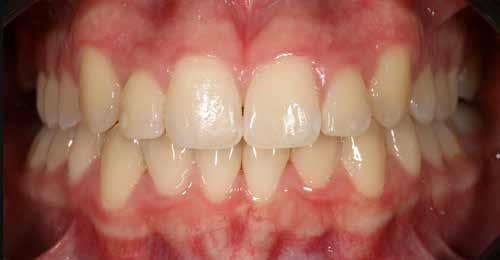

A fix fogszabályozó készülék mindössze 16 hónapos kezelés után került eltávolításra! Páciensünk legnagyobb örömére állcsontműtét nélkül sikerült mind az arcesztétikai, mind a funkcionális rehabilitáció (13–18. képek)